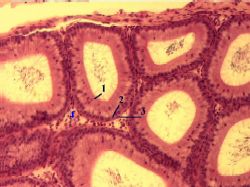

| 2,а. Препарат - придаток яичка. Окраска гематоксилин-эозином.

а) Выносящие канальцы яичка (1), как и было сказано в таблице, отличаются

неровным контуром просвета.

б) С другой стороны снимка – проток придатка (2), который вследствие своей извилистости многократно попадает в плоскость среза;

у его просвета – чёткие контуры.

| (Малое увеличение)